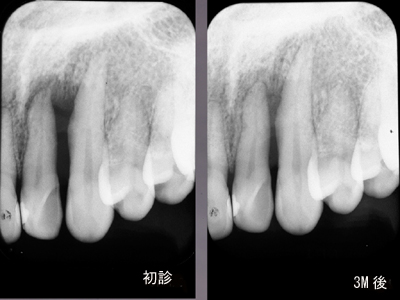

咬合性外傷

左上犬歯近心の骨欠損です。

EPT+.プラークコントロールが非常に良い方で赤染めではほとんどどこも染まりません。

ブラキシズムによる外傷と診断し、スケーリング、ルートプレーニングは一切せずナイトガードと自己暗示療法による外傷のコントロールを試みました。

初診と3ヶ月後の比較です。骨が少しずつ戻ってきました。